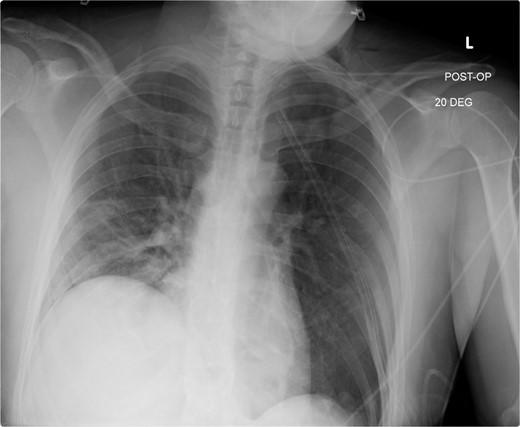

This is a case of a 26-year-old male patient who presented with symptoms of dyspnea on exertion, left chest pressure, and constipation for 7 years. He was a never smoker with no history of trauma, nor prior neck and chest surgeries. Baseline pulmonary functions tests revealed FEV1 of 71% predicted and DLCO of 77% predicted. Work-up included a computed tomography (CT) of the chest which revealed marked left hemidiaphragm elevation with compression atelectasis of the left lower lobe (Fig. 1). A fluoroscopic sniff test showed paradoxical movement of the left hemidiaphragm consistent with diaphragmatic paralysis. Interestingly, abdominal imaging obtained 14 months before surgery showed a displaced stomach but without volvulus (Fig. 2). Due to the impact on the patient’s quality of life, he was offered surgical treatment with a robotic-assisted left thoracoscopic plication of the diaphragm. This was done using a three-arm technique using the Da Vinci Xi surgical system (Intuitive Surgical, Sunnyvale, CA) with an additional assistant port. Plication was performed by placing multiple horizontal mattresses sutures reinforced with pledgets in an anterior–posterior orientation, and systematically working medial to lateral. A postoperative chest X-ray showed a satisfactory result (Fig. 3).

Immediate post-operative film demonstrates intact repair, and well-positioned chest-tube.